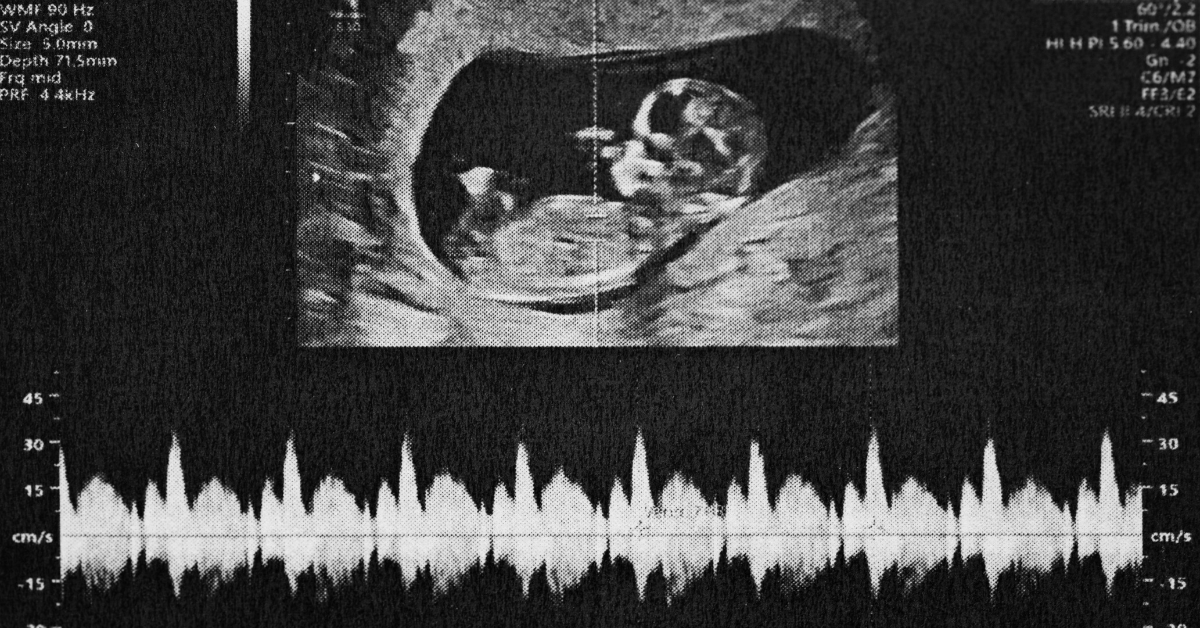

Ultrasounds offer further insight into development while allowing parents glimpses into their baby’s world before birth—often revealing critical information regarding growth rather than focusing solely on sex determination at this stage.